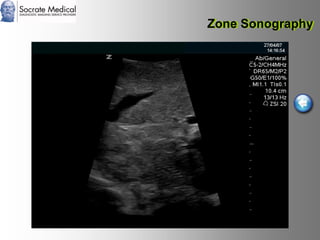

Il documento presenta la tecnologia della zone sonography, che promette una rivoluzione nel campo degli ultrasuoni, superando i limiti dei sistemi tradizionali grazie a metodi di acquisizione dati più veloci e una gestione delle informazioni migliorata. Questa tecnologia consente una maggiore definizione dell'immagine, una riduzione degli artefatti e un'ottimizzazione del processo diagnostico, con vantaggi in termini di tempo e costi. Inoltre, il channel domain processing e la zone speed technology offrono applicazioni avanzate e miglioramenti nella sicurezza diagnostica.